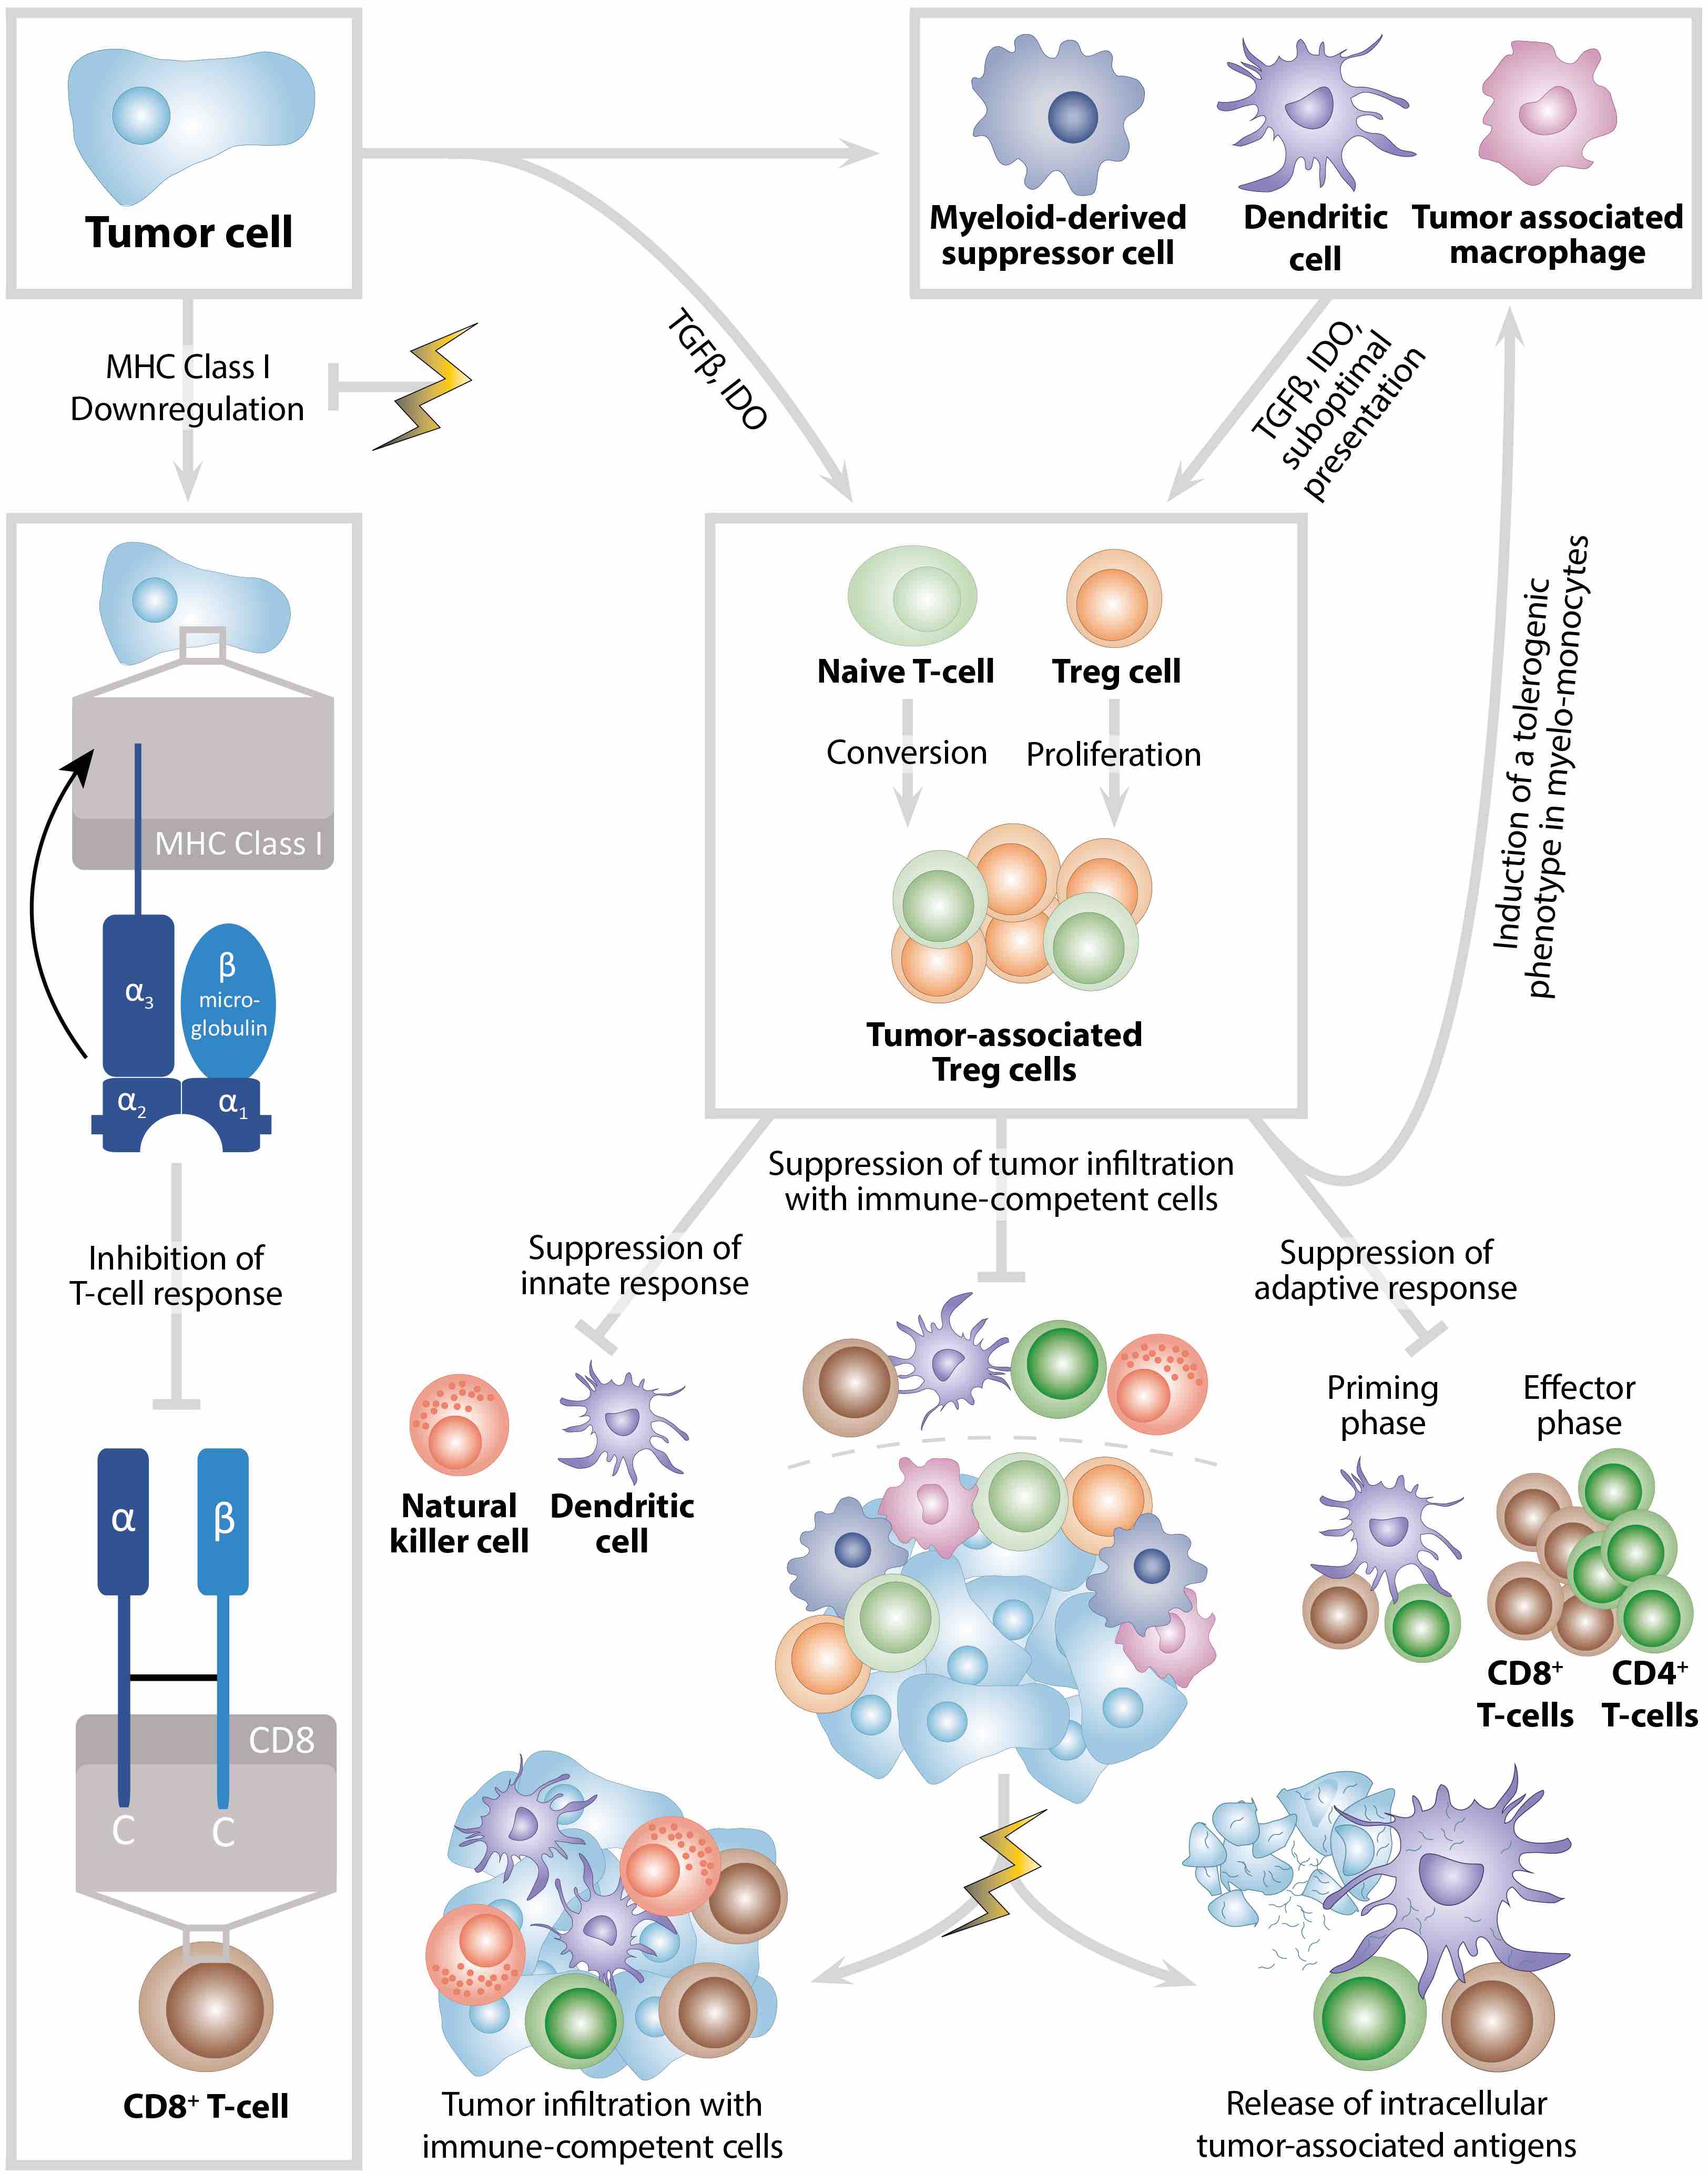

Despite continuous scientific efforts, the possibilities to treat large, advanced tumors are still limited. Especially tumor metastasis, which is the main cause of cancer death, and tumor immune evasion represent major challenges of cancer treatment.

Radiotherapy may overcome the immunosuppressive tumor microenvironment by enhancing perfusion and oxygenation of the tumor and releasing tumor-associated antigens from apoptotic or necrotic tumor cells. In addition, radiotherapy fosters expression of MHC Class I molecules on tumor cells. Together, this leads to increased immune cell infiltration into and immune cell activation in the tumor.

Anecdotal clinical reports suggest that local tumor irradiation alone may also exert systemic or abscopal anti-tumor immune effects with subsequent control of non-irradiated metastases. This study used a syngeneic mouse model with a primary irradiated and a secondary non-irradiated tumor to study abscopal effects of local radiotherapy combined with RNActive® vaccination.